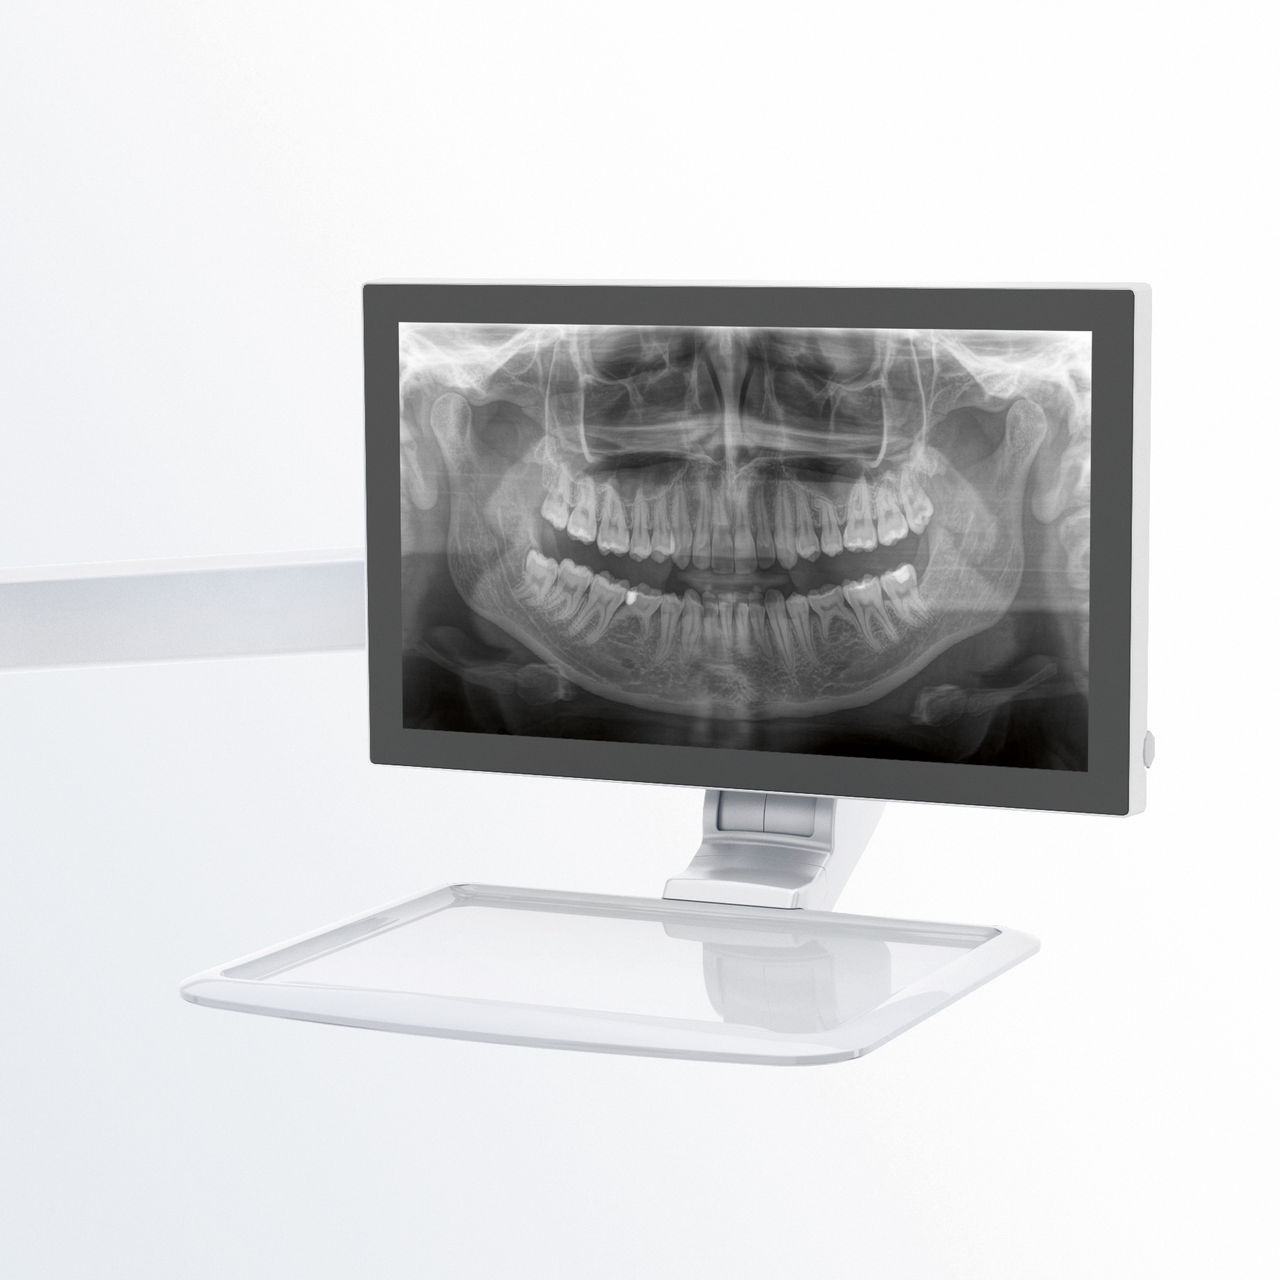

Es muy importante que tanto los pacientes como el personal médico dispongan de unos procedimientos agradables y relajados. Hay una gran satisfacción y motivación cuando las cosas salen bien, tal y como estaban previstas. El uso de Orthophos o Axeos con Sidexis 4 te proporciona una asistencia dirigida. Los sistemas de radiología son simples de usar, con unas posibilidades de diagnóstico únicas. Así, se garantiza que todos los aspectos del proceso de tratamiento creen una experiencia positiva.

Un correcto posicionamiento del paciente contribuye a mejorar su experiencia, ya que con imágenes de alta calidad se consigue un diagnóstico más preciso.

Este concepto de 10 puntos facilita la colocación del paciente y la adquisición de imágenes radiológicas. Se fundamenta sobre todo en dos aspectos: unas imágenes de alta calidad y la mayor comodidad para el paciente y el asistente.